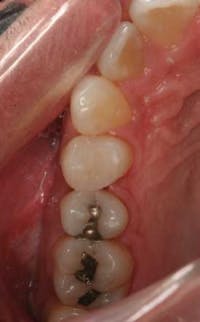

The study used only one shade of composite — A2. Due to the “chameleon effect” of the composite, 100% of the restorations were deemed esthetically acceptable. As a result of the high compressive strength values reported out of Nova University, restorations were placed in all areas of the posterior dentition ranging from first bicuspids through third molars.

After traditional finishing and polishing techniques, all of the restorations placed were evaluated and demonstrated clinically acceptable marginal integrity.

This marginal integrity was especially evident on three-month and six-month recall radiographs. SonicFill composite demonstrates a high radiopacity and can be clearly distinguished from enamel, dentin, and recurrent caries.